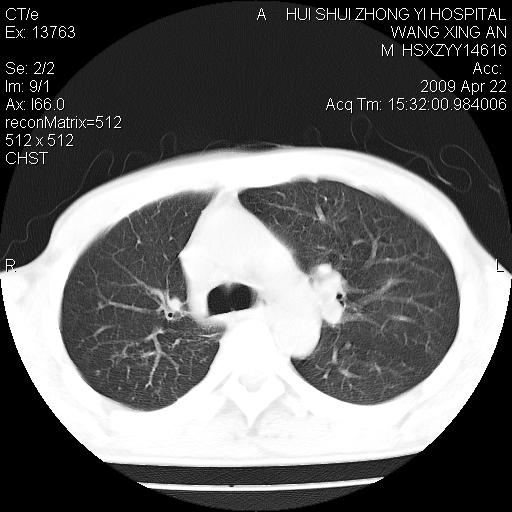

标题: CT19534:患者男、46岁咳嗽、胸痛半月。 [打印本页]

标题: CT19534:患者男、46岁咳嗽、胸痛半月。

1、右下肺中央型肺癌并右肺转移,右肺下叶不张。(右肺有结节影)。

2、右中上肺陈旧性肺结核(因为大多为纤维灶)。

3、右侧胸腔积液。

1、右下肺中央型肺癌并右肺转移,右肺下叶不张。(肿块围绕右肺下叶支气管生长,致管腔闭塞右肺下叶不张;右肺有结节影)。

2、右侧胸腔积液。

3、右中上肺陈旧性肺结核(右肺见纤维化病灶及点状钙化)。